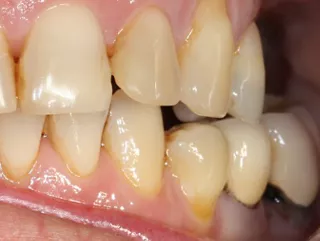

3a-b & 4a-b. Preoperative situation.

Free-end saddle. Periodontal tissue appeared healthy. Plenty of keratinized tissue. Notice the more extensive vestibular bone loss around 25.